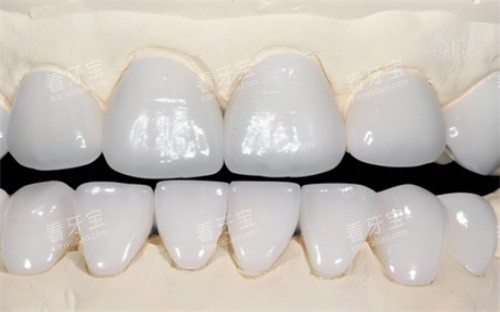

全口吸附性义齿是一种采用特殊设计的修复体,通过功能性印模技术和边缘封闭系统,在口腔内形成稳定的负压吸附力,使假牙能够紧密贴合牙槽骨黏膜表面。与传统活动假牙相比,它的稳固性和舒适度都有显著提升,外观也更接近自然牙齿。